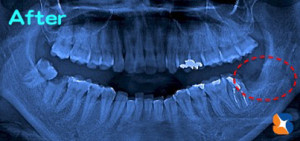

抜歯後のレントゲン

コラム「抜歯後のレントゲン」の画像